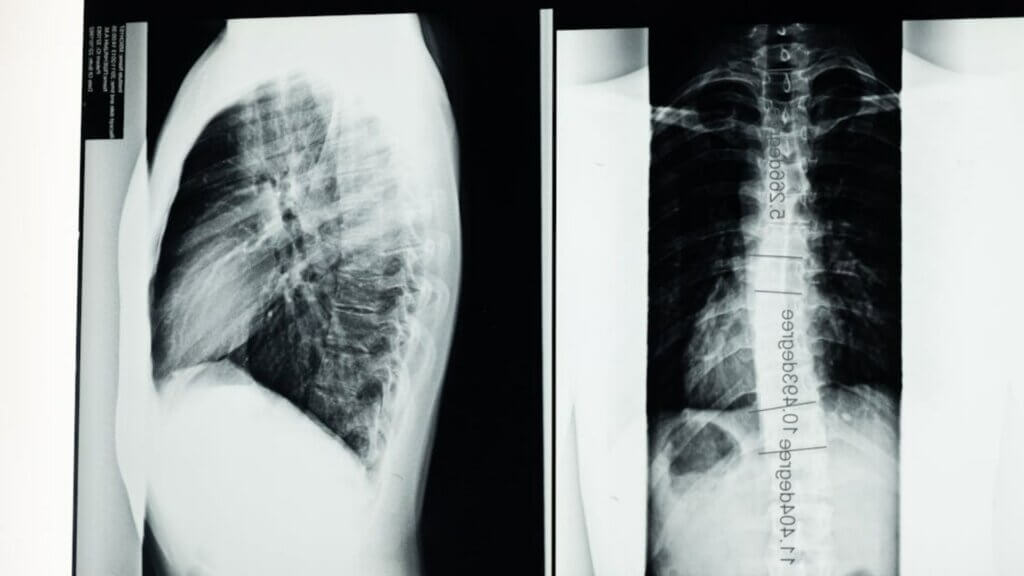

A spinal cord stimulator is not a simple device to replace or repair. According to Hopkins Medicine, a spinal cord stimulator works by delivering small electrical impulses to the spinal cord to interrupt chronic pain signals, typically after other treatments have failed. It consists of thin wires and a small, pacemaker-like battery, and patients control it themselves using a remote when pain flares.

Patients With Stimulators Are Supposed to Be Able to Skip the Scanner

The complaint states Thomas suffered injuries requiring medical treatment, including surgery, following the incident. Replacing or repairing a spinal cord stimulator is no minor procedure. According to Hopkins Medicine, implantation alone takes one to two hours and involves placing electrodes in the epidural space of the spine. Recovery typically spans two to four weeks before incisions fully heal.